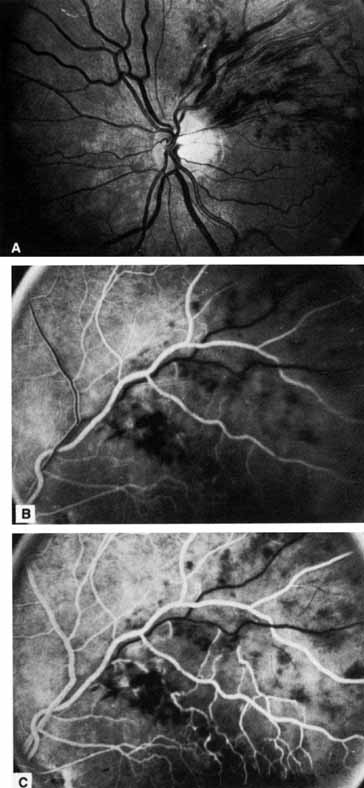

Fig. 2 A. Nonischemic central retinal vein occlusion. Note venous engorgement, dot, blot, and flame-shaped hemorrhages, blurring of disc margins, and a hemorrhage overlying the macula. B. Fluorescein angiogram reveals mild venous engorgement and tortuosity with virtually no capillary nonperfusion.

The ophthalmoscopic features of nonischemic central retinal vein occlusion are similar to those of ischemic central retinal vein occlusion, but are much less extensive (see Fig. 2; Fig. 3A and 3B). Engorgement of the venous tree (including the capillaries) is prominent; there is increased tortuosity and dilation and a darker appearance of the blood column. Retinal hemorrhages vary markedly. Sometimes they occur only peripherally; at other times, they may be rather prominent in the posterior pole.60 Cotton-wool spots are rare. Vision may be decreased because of macular edema or macular hemorrhage.

Fig. 3 A and B. Acute nonischemic central retinal vein occlusion in a 36-year-old hypertensive man. His visual acuity was 20/200. C and D. Six weeks later, he presented with eye pain, decreased vision, and neovascular glaucoma. The type of occlusion now is ischemic.

The angiographic pattern may show little except occasionally a prolonged venous transit time. Dilation of the retinal venous circulation, mild staining of the walls of veins, and varying degrees of disc and macular edema may be present (including cystoid macular edema). Capillary nonperfusion is not a prominent feature, nor is its sequela, neovascularization. The electroretinogram is nearly normal, confirming the lack of ischemia.77 The intraocular pressure is frequently lower on the side of the occlusion.78 Synonyms for this type of central retinal vein occlusion have included partial, incomplete, imminent, threatened, incipient, or impending central retinal vein occlusion.60,76 How many central retinal vein occlusions in this category are actually incomplete or partial occlusions that then progress to a more complete occlusion is unknown. It does appear that some eyes with nonischemic central retinal vein occlusion go on to develop a more ischemic type of central retinal vein occlusion (see Fig. 3); whether this represents a progression of the vein occlusion62 or simply progressive retinal capillary nonperfusion is unknown. In series in which the incidence of conversion for the nonischemic occlusion to the ischemic type has been studied, the incidence ranges from approximately 5% to 22%, depending on the duration of follow-up, and is higher for older patients.63,74,79–81